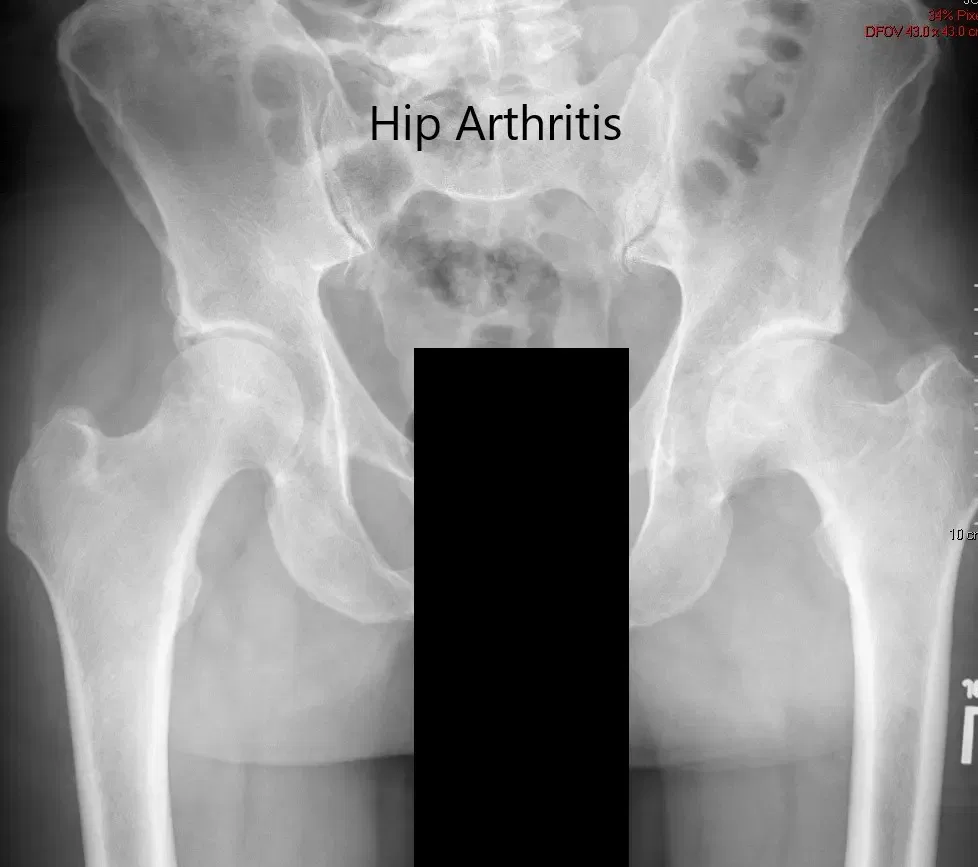

Las imágenes revelaron osteoartritis severa en la cadera izquierda con quistes subcondrales, esclerosis y osteófitos. El acetábulo izquierdo era poco profundo con el cuello femoral izquierdo acortado.

Radiografía preoperatoria de la pelvis que muestra una vista AP de la pelvis con ambas caderas.